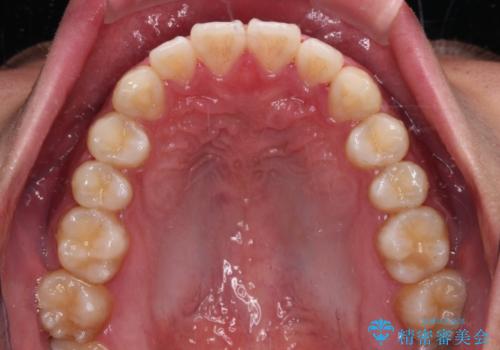

- 20代男性

- インビザライン・ライト

- 8ヶ月

- 上下前歯の叢生を気にして来院された患者様です。

費用を抑え、期間もあまりかけずに治療をしたいとのことで、インビザライン・ライトを用いて矯正治療を行うこととしました。